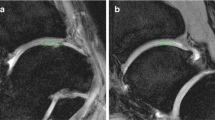

The ROIs were measured at all levels, from the cartilage surface to the deep zones, and the subchondral bone was excluded carefully. Each ROI was measured within a range that measured 55 voxels high and 40 voxels wide [5,8] (Figure 1). We evaluated and recorded the Outerbridge grade of the damaged areas of cartilage during surgery, confirmed arthroscopic photographs during measurement of cartilage damage using MRI, and had another doctor reevaluate the Outerbridge grade. Three orthopaedic surgeons and one radiologist, having board certificate of The Japanese Orthopaedic Association and Japan Radiological Society, separately measured the areas of cartilage damage on the MRI. To minimize disparities, the measurements were obtained three times and the mean value calculated.

A 21-year-old man sprained his knee while kickboxing. Five months later, he landed awkwardly in a hurdle touchdown and sprained his knee again. Giving way persisted and investigations revealed a right anterior cruciate ligament (ACL) injury and right medial meniscus injury. The patient was treated with ligament reconstruction and meniscal suture (Figure 4).

DT imaging in the early cartilage damage. The patient underwent surgery for right knee ACL and medial meniscus injury. In the inner femoral condyle, a cartilage crack caused by the medial meniscus rupture was observed to have Outerbridge grade 1 damage. The ADC for this area was measured as 1.75 × 10−3 mm2/s.